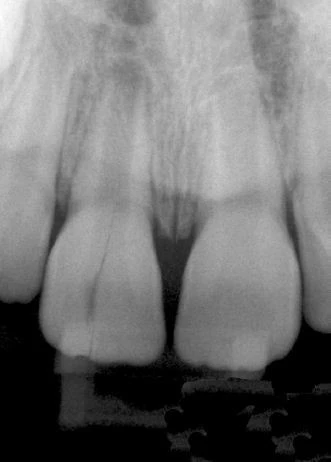

Hình 5. Răng không mang miếng trám hoặc mang miếng trám nhỏ, răng không sâu răng hoặc sâu nhỏ nhưng tuỷ răng bị hoại tử.

Hình 6. Răng đã điều trị nội nha là một phần của phục hình cầu răng vói